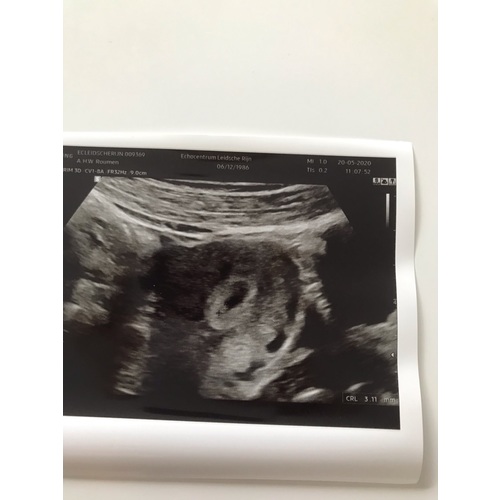

Dit was 5 weken ong en ik kon niet veel zien maar wel iets gelukkig 9 juni weer een echo hopen op een kloppende hartje